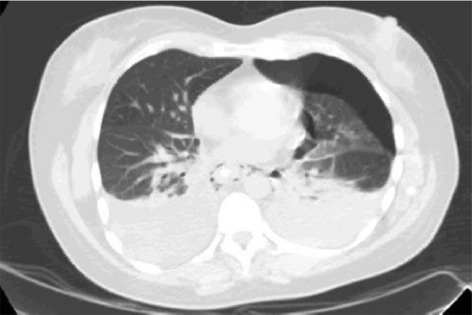

Result: The comparative analysis of the data shows a decrease in the number of presentations in ESU of AC cases during the pandemic, compared to the previous year, most often due to patients' fear of contacting the virus in the hospital environment. The median time between the onset of symptoms and the presentation in the ESU: 2020 – 14 days, 2019 – 5 days. Forms of moderate and severe AC predominated in the pandemic: GradeI—14.28%; GradeII—57.14%; GradeIII—28.57%. In 2019 GradeI—66.39%, GradeII—27.73%, GradeIII—5.88%. Laparoscopic cholecystectomy was attempted for all patients from the beginning, but the complications identified during surgery and severe forms led to a conversion rate in 2020 of 14.28%, compared to 5.88% in 2019. The severity of the cases is also observed in the postoperative complications encountered (perihepatic abscess Fig. 2. Figure 2, wound infection, bile leak; 2019—5.04%, 2020—23.21%), which required surgical reinterventions to solve them (2019: 2.52%, 2020: 10.71%). The number of deaths was significantly higher in 2020 (5.35%), compared to 2019 (0.84%).